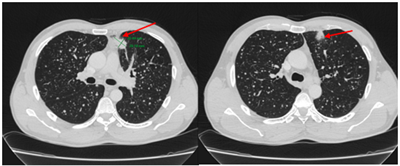

Case lâm sàng: Ứng dụng trí tuệ nhân tạo (Artificial intelligence – AI) trong chẩn đoán và điều trị sớm Ung thư phổi tại Trung tâm Y học hạt nhân và Ung bướu, Bệnh viện Bạch Mai

Theo GLOBOCAN 2022, ung thư phổi đứng đầu về số ca mới mắc (2.480.301 ca mới mắc chiểm 12.4%) và dẫn đầu số ca tử vong (1.817.172 ca tử vong chiếm 18.7%) trên toàn thế giới.  Tại Việt Nam tỷ lệ mắc ung thư phổi xếp thứ ba 13,5% lệ tử vong...